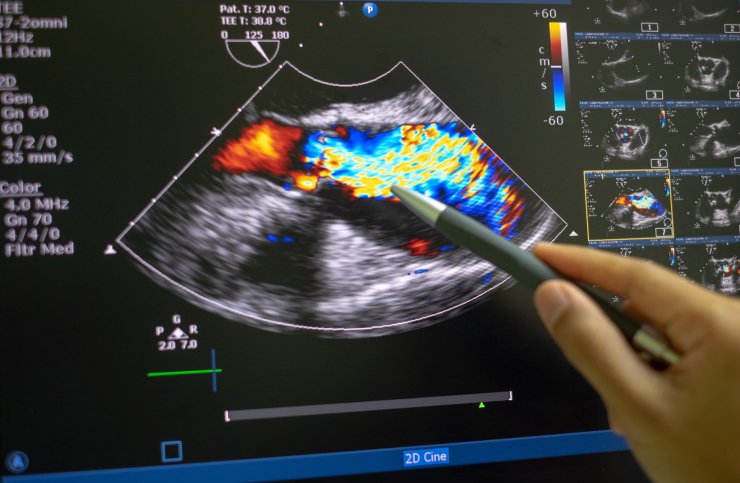

Patienten mit einer Rheumatoiden Arthritis (RA) haben offenbar ein erhöhtes Risiko, eine Aortenklappenstenose (AS) zu entwickeln. Das zeigt eine Kohortenstudie aus den USA, für welche rund 73.000 RA-Patienten mit knapp 640.000 nach Alter und Geschlecht gematchten Personen ohne RA verglichen wurden.